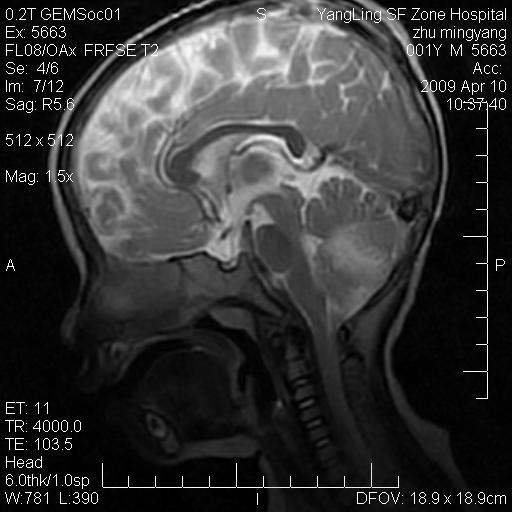

患者:1岁半,两天前外伤收住我院,ct检查小脑占位

考虑星形细胞瘤,建议增强

髓母细胞瘤或血管母细胞瘤,增强后可以鉴别;影像资料见 <。鱼博浪老师的《中枢神经系统ct与mr鉴别诊断》 小脑部肿瘤章节。

髓母细胞瘤或血管母细胞瘤!支持!

支持考虑髓母细胞瘤

考虑----髓母细胞瘤可能性大

考虑髓母细胞瘤或室管膜瘤。

支持髓母细胞瘤。

考虑髓母细胞瘤。

考虑髓母细胞瘤或星形细胞瘤

考虑髓母细胞瘤.

考虑髓母细胞瘤可能性大。

小脑肿瘤.考虑髓母细胞瘤可能.

就病灶部位及临床资料首先考虑髓母.